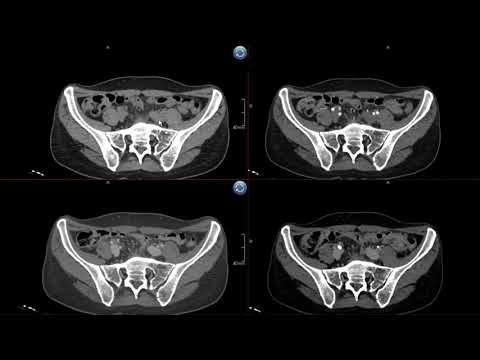

В данной лекции я рассказываю о методике проведения компьютерной томографии. Подробно рассматриваю вопросы организации работы отделения лучевой диагностики на примере кабинета КТ. Рассматриваются все этапы проведения лучевого исследования от момента записи пациента на исследования до написания заключения.